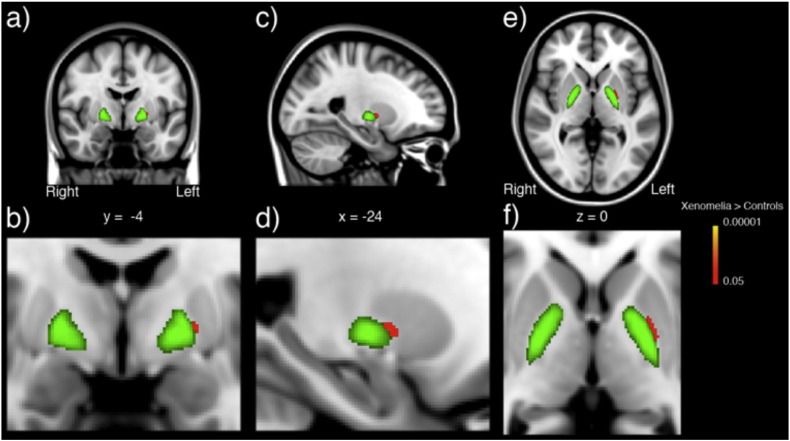

A cluster in the dorsomedial part of the left putamen showed local thinning in participants suffering from xenomelia compared with control men ( Fig. 1, Fig. 2).

Local thinning of the left putamen in xenomelia. A cluster showing significant dorsomedial thinning (red-yellow) of putamen (green) in participants with xenomelia compared with healthy control men. Error probability was set at p < 0.05 corrected for multiple comparisons using 5000 permutations of the group label across space. The shape differences and putamen masks are overlaid on the MNI152 T1-weighted template. a) Coronal plane unzoomed b) coronal plane zoomed c) sagittal plane unzoomed d) sagittal plane zoomed, e) axial plane unzoomed, f) axial plane zoomed. x, y, z, coordinates of the Montreal neurological institute (MNI) space. (For interpretation of the references to color in this figure legend, the reader is referred to the web version of this article.)

The significantly (p = 0.005, corrected for multiple comparisons) thinner dorsomedial part of the left putamen (MNI peak coordinates: x = − 21, y = − 2, z = 7) in xenomelia participants is located in that part of the putamen, which represents foot movement activity as has been reported by Gerardin and colleagues ( Gerardin et al., 2003 ) (MNI peak coordinates: x = − 30, y = 0, z = 10). There was also a trend (p = 0.063, corrected) towards a thinner right dorsomedial putamen. Additionally, a trend (p = 0.060, corrected) towards local thinning of the left ventromedial caudate nucleus was found in participants with xenomelia and is depicted in Fig. 2 .